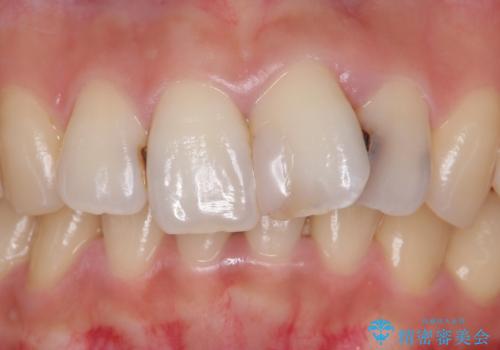

- 前歯をきれいにしたいとのご希望により来院された患者様です。

ご希望により、上の前歯4本のセラミッククラウンによる補綴治療を行いました。

- ¥572,000 (根管治療×1本、土台×1本、仮歯×4本、クラウン×4本) ※税込費用は治療当時の料金となります